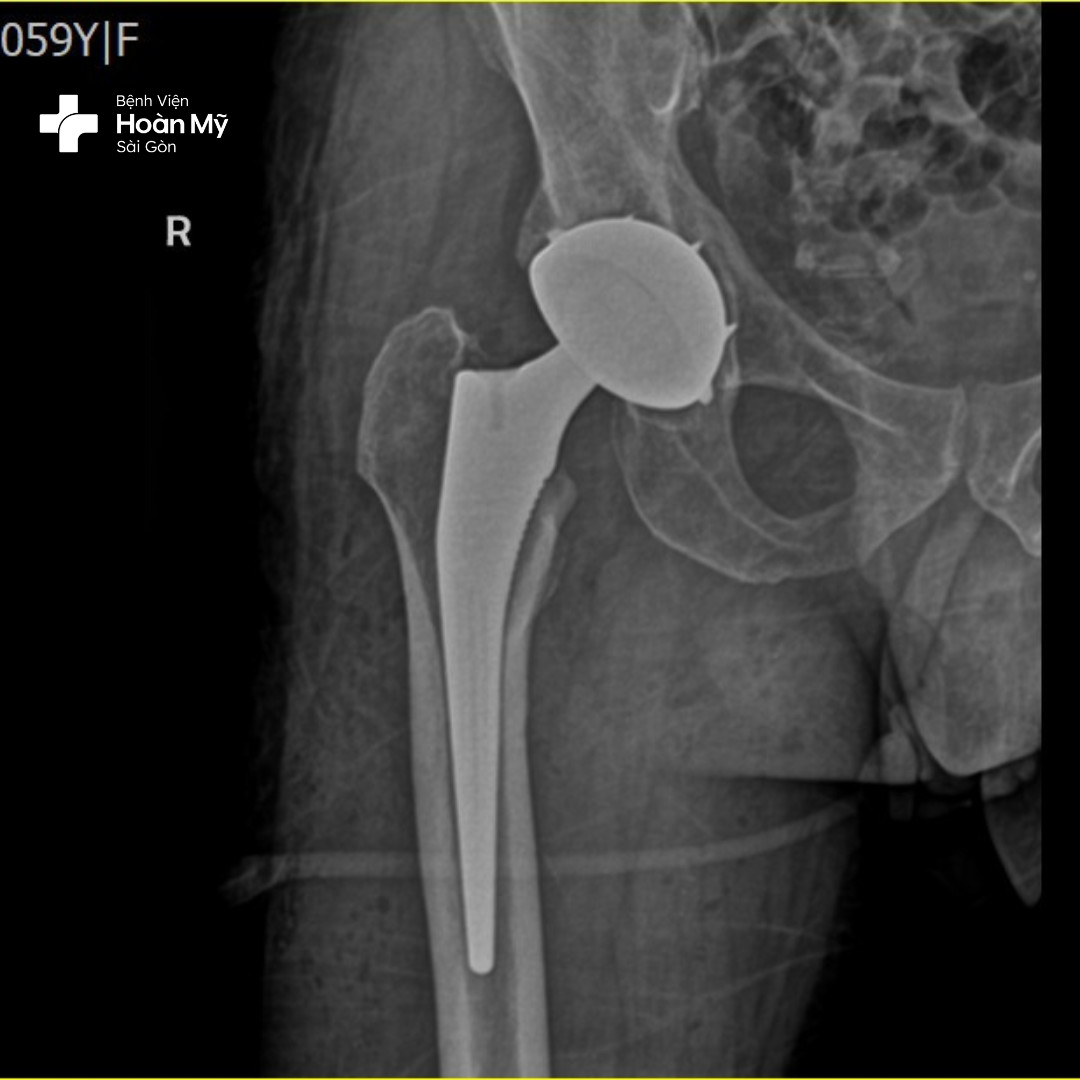

Hình ảnh X-quang sau phẫu thuật thay khớp háng của người bệnh

Kỹ thuật tiên tiến này được thể hiện trong quá trình phẫu thuật thay khớp háng, bác sĩ phẫu thuật chỉnh hình tại bệnh viện Hoàn Mỹ Sài Gòn sẽ THAY THẾ cả HAI đầu khớp háng bị hư hỏng bằng các bộ phận nhân tạo cùng một lúc giúp người bệnh không phải chịu đau 2 lần, tránh được biến chứng phẫu thuật, tiết kiệm về tài chính. Đây là kỹ thuật đòi hỏi tay nghề cao của bác sĩ có nhiều năm kinh nghiệm.